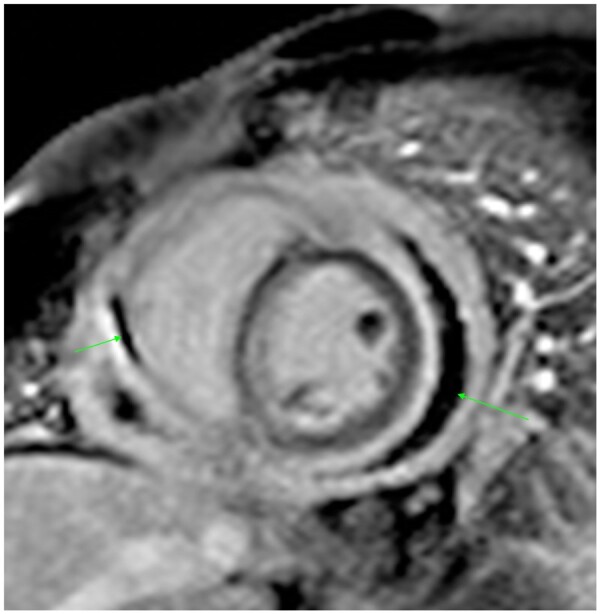

Figure 7.

Delayed enhancement short axis view in a 66-year-old male patient with long-standing hypertrophic cardiomyopathy. Note the increased thickness of the septum (here measured 17 mm) and the strong enhancement of both anterior and inferior walls of the left ventricle (green arrows).